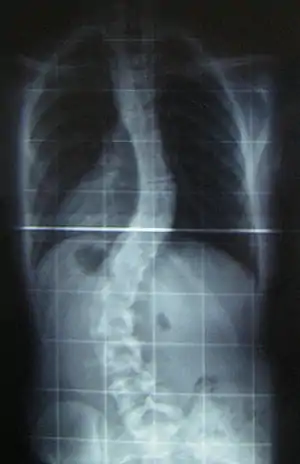

Сколіоз

Сколіо́з (англ. scoliosis, походить від грец. σκολιός — «викривлення») — захворювання опорно-рухового апарата, що характеризується викривленням хребта у фронтальній (боковій) площині з розворотом хребців (торсія) навколо своєї вертикальної осі. Процес формування сколіотичної деформації — це результат взаємодії чинників, що порушують вертикальне положення хребта, й пристосувальних реакцій, спрямованих на збереження вертикального положення. Приблизно у 80 % усіх випадків причина виникнення викривлень невідома.

![]() Рентгенограма Рентгенограма | |